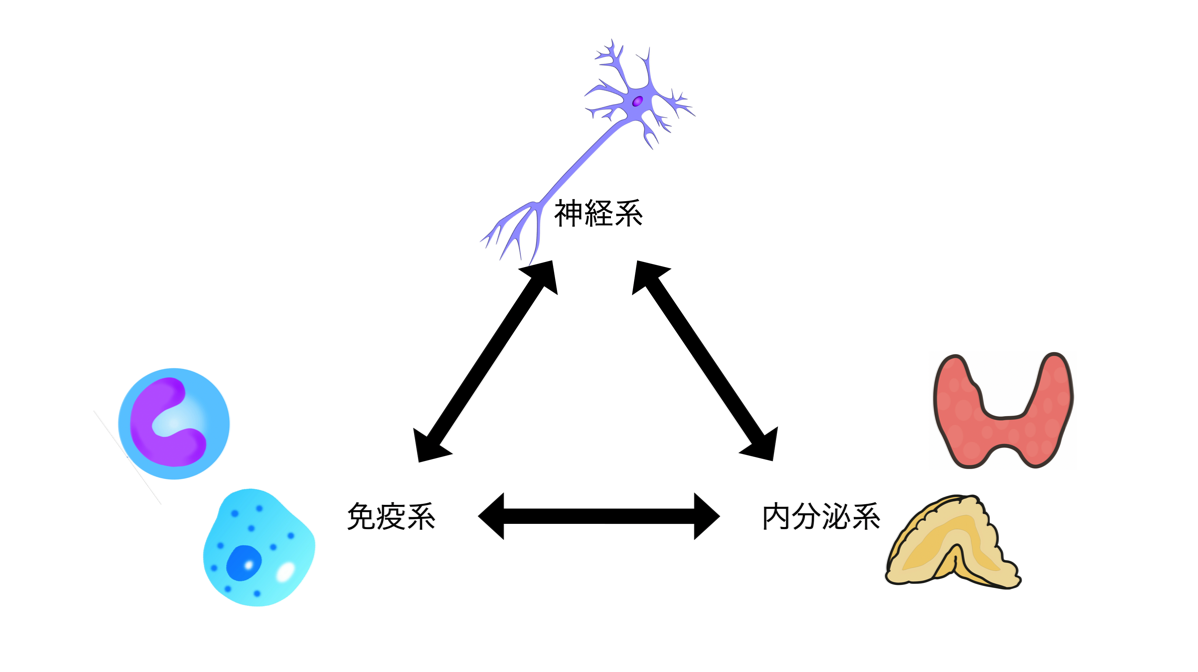

神経ー免疫ー内分泌コネクション

ところで免疫系は神経系や内分泌系と相互に繋がりを持っています。例えば自律神経の終末部では、免疫細胞に情報伝達しています。免疫細胞もサイトカインと言う情報伝達物質で脳を含め全身に情報を伝えています。神経が有線連絡ならサイトカインが無線連絡という具合です。あるいは閉経で女性ホルモンが低下すると炎症が亢進します。もちろん、内分泌臓器間での繋がりもあります。

例えば、精神的あるいは肉体的なストレスでは炎症が亢進し、コルチゾールの分泌が高まります。副腎が疲弊してもはやコルチゾールが十分に作れなくなってしまうと、バーンアウト(Burn out) で疲労の極致です。つまり、抗炎症を図るためには免疫系だけを見ているだけでは不十分です。イタズラに免疫強化と言って、鞭を打ちすぎて、かえって免疫細胞の疲弊を招いているようなことはありませんか?

うつ状態や不眠の背景には、慢性炎症や慢性ストレス、女性ホルモンの低下があるのかもしれません。

ところで免疫系は神経系や内分泌系と相互に繋がりを持っています。例えば自律神経の終末部では、免疫細胞に情報伝達しています。免疫細胞もサイトカインと言う情報伝達物質で脳を含め全身に情報を伝えています。神経が有線連絡ならサイトカインが無線連絡という具合です。あるいは閉経で女性ホルモンが低下すると炎症が亢進します。もちろん、内分泌臓器間での繋がりもあります。

例えば、精神的あるいは肉体的なストレスでは炎症が亢進し、コルチゾールの分泌が高まります。副腎が疲弊してもはやコルチゾールが十分に作れなくなってしまうと、バーンアウト(Burn out) で疲労の極致です。つまり、抗炎症を図るためには免疫系だけを見ているだけでは不十分です。イタズラに免疫強化と言って、鞭を打ちすぎて、かえって免疫細胞の疲弊を招いているようなことはありませんか?

うつ状態や不眠の背景には、慢性炎症や慢性ストレス、女性ホルモンの低下があるのかもしれません。